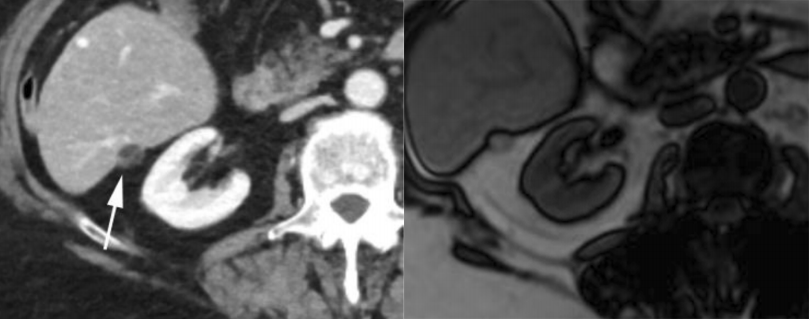

肝血管瘤为最常见的良性肿瘤,可分为海绵状血管瘤、毛细血管型血管瘤、硬化型血管瘤等。包膜皱缩为肝血管瘤的不典型表现,可见于肝硬化背景下及硬化型血管瘤,后者被认为是血管瘤退化末期,表现为透明化纤维组织替代血管周围间隙。影像上表现为 T2WI 信号减低,增强后缺乏典型填充式强化。

硬化型血管瘤,CT 表现为低密度,增强后无强化,邻近肝包膜凹陷,MRI T2-FS 序列示病灶呈高信号。该患者既往直肠癌病史,此病灶不能除外转移。活检结果为硬化型血管瘤。

肝上皮样血管内皮瘤为罕见的间质来源具有恶性潜能的肿瘤,恶性程度介于血管瘤与血管肉瘤之间。以女性好发,中位年龄为 30-50 岁。病理上肿瘤内部含有丰富的纤维成分,纤维收缩可牵拉邻近肝包膜出现肝包膜的凹陷。

影像特征:(1)常多发,且多位于肝包膜下,较大结节多有融合趋势。(2)晕征:CT 动态增强上动脉期病灶边缘环形强化,门脉期显示为晕征,即中心为更低密度,中层为较明显强化环,最外层为低密度带。MRI 增强上病灶中央和边缘低信号,其间夹杂环形高信号强化带,形成晕征,病理上对于肿瘤外周部为细胞活跃增生区,中央为硬化区。(3)棒棒糖征:尤其是门脉期,正常肝静脉或门脉分支进入病灶边缘并终止于病灶。

肝上皮样血管内皮瘤,MRI 示病灶邻近肝包膜,呈 T1WI 低信号、T2-FS 中等信号,增强后动脉晚期云絮状强化,门脉期呈持续性强化,邻近肝包膜凹陷。